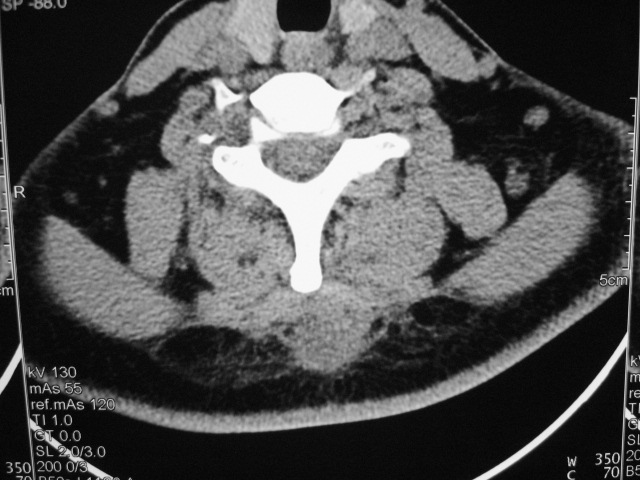

女,46岁,发现颈后区肿块3月余.

颈后软组织肿块,内可见坏死区及点状钙化,邻近颈椎棘突可见破坏,邻近肌间隙模糊,肿块周围脂肪间隙可见索条状影。

考虑:1)感染,结核可能;

2)肿瘤不能排除。